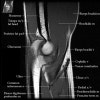

팔꿈치 관절의 MRI 단면 영상

- Sagittal section

1) Biceps Brachii tendon and Brachiallis muscles

2) Radial head for radiographically occult fractures

3) Distal Triceps tendon